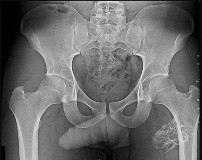

Question 39

A 12-year-old obese male undergoes in-situ percutaneous screw fixation for a unilateral Slipped Capital Femoral Epiphysis (SCFE). Prophylactic pinning of the contralateral, asymptomatic hip is considered. Which of the following patient profiles is the strongest indication for prophylactic contralateral pinning?

Explanation

The risk of developing a contralateral SCFE is significant (around 20-30%, higher in certain populations). Strong indications for prophylactic pinning of the contralateral hip include patients with underlying endocrinopathies (e.g., hypothyroidism, renal osteodystrophy, growth hormone deficiency), patients presenting at an unusually young age (males < 10, females < 9), and patients who are unreliable for follow-up. Obesity alone, while a risk factor for the primary slip, is not an absolute indication for prophylactic pinning.